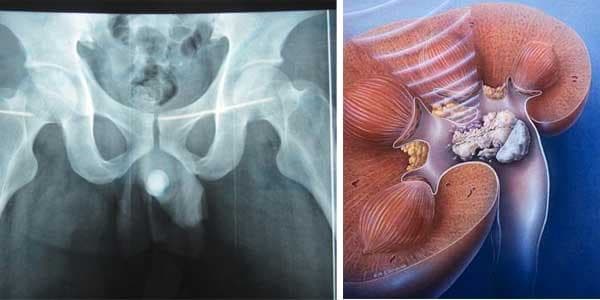

Sỏi niệu đạo chiếm tỷ lệ ít nhất trong bệnh lý sỏi tiết niệu, chỉ xấp xỉ 5%. Tuy nhiên, bệnh cũng gây ra những biến chứng nguy hiểm cho sức khỏe nếu không được điều trị kịp thời. Vậy đâu là nguyên nhân gây bệnh, triệu chứng cũng như cách điều trị bệnh như […]

Sỏi niệu đạo chỉ chiếm 4% số người mắc sỏi đường tiết niệu nhưng sỏi có thể gây nên nhiều bất tiện, khó chịu, thậm chí gây nên những hậu quả nghiêm trọng tới sức khỏe nếu không được tìm hiểu và điều trị kịp thời. Vì vậy, bài viết sau đây sẽ cung cấp […]

Sỏi niệu đạo là bệnh lý thường gặp ở nam giới, 1/3 sỏi nằm ở niệu đạo sau còn 2/3 nằm ở niệu đạo trước. Triệu chứng của sỏi niệu đạo là gì là vấn đề được đông đảo bạn đọc quan tâm. 1. Sỏi niệu đạo là gì? Niệu đạo là một ống dẫn […]